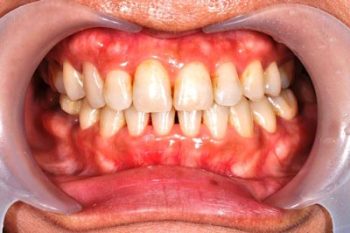

治療後

治療結束後,可見下顎已恢復至正常位置